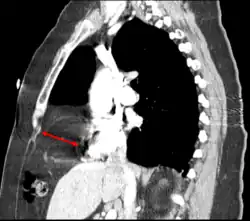

The Bochdalek hernia, also known as a postero-lateral diaphragmatic hernia, is the most common manifestation of CDH, accounting for more than 95% of cases. In this instance the diaphragm abnormality is characterized by a hole in the postero-lateral corner of the diaphragm which allows passage of the abdominal viscera into the chest cavity. The majority of Bochdalek hernias (80–85%) occur on the left side of the diaphragm, a large proportion of the remaining cases occur on the right side. To date, it carries a high mortality[3] and is an active area of clinical research.

This rare anterior defect of the diaphragm is variably referred to as a Morgagni, retrosternal, or parasternal hernia. Accounting for approximately 2% of all CDH cases, it is characterized by herniation through the foramina of Morgagni which are located immediately adjacent and posterior to the xiphoid process of the sternum.[4]